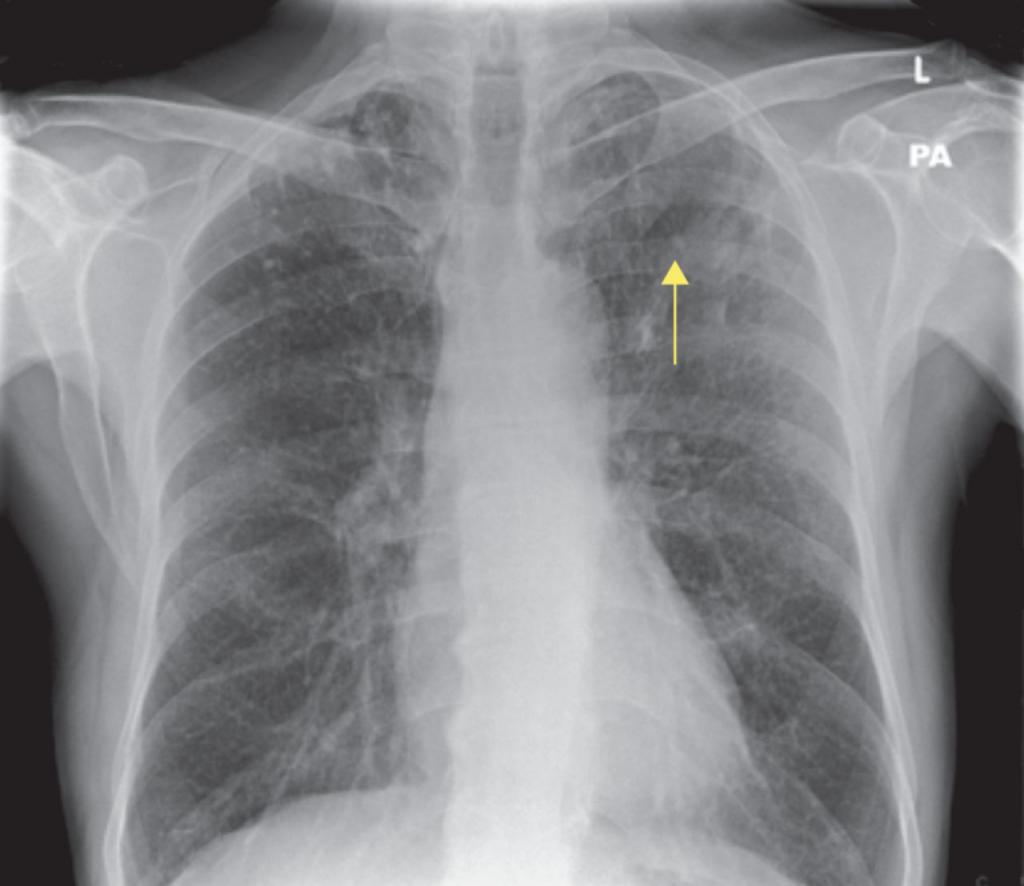

При рентгеновском излучении лёгких, поражённых коронавирусной инфекцией, наблюдаются затемнения в нижней части органа (на снимке обозначаются белыми пятнами). Пятна называются симптомом “матового стекла”. На рентгене видны пятна, которые обуславливаются наличием жидкости в лёгких.

Симптом “матового стекла” в легких

Симптом “матового стекла” проявляется у больных на фоне поражения лёгких вирусом. Так как дыхательный орган подвергается серьёзным изменениям, в нём появляются зоны повреждений.

Снижается плотность лёгочной ткани. В поражённом участке проявляется умеренно-сниженная воздушность, главным признаком выступает видимость сосудов лёгких и стенок бронхов.

Заметить данный симптом на рентгене сложно, поэтому требуется дополнительно сделать компьютерную томографию.

Ниже представлены фото, как выглядит симптом “матового стекла” на рентгене и компьютерной томографии: